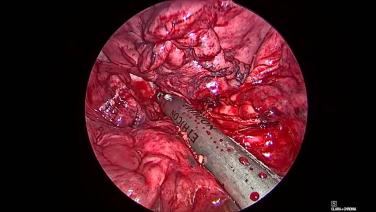

Thorascopic Lobectomy - Complete the Lymphadenectomy